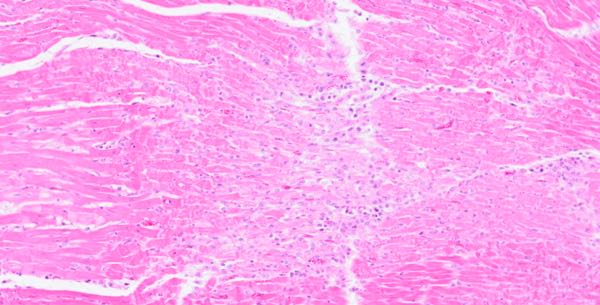

Heart histology (Image 6) of the ram lamb indicated marked, acute, multifocal to coalescing, monophasic myonecrosis with acute, diffuse myocardial degeneration and early repair. This change varied in severity with milder changes occurring in ewes that died earlier in the investigation, and more dramatic cardiac lesions with early repair in animals that took several days to die. Histologic changes of the liver and kidney of all animals examined were also present. Glomerular shrinkage with severe protein loss and tubular degeneration (Image 7) was observed in the kidneys. Liver sections revealed acute, diffuse, mild-to-moderate hepatic degeneration. Moderate, acute, multifocal pulmonary oedema was present in one ewe. Changes visible in the kidney, liver, and lung were attributed to hypoxic damage associated with circulatory failure due to the cardiac disease. Myoglobinaemia may have contributed to the renal lesions.